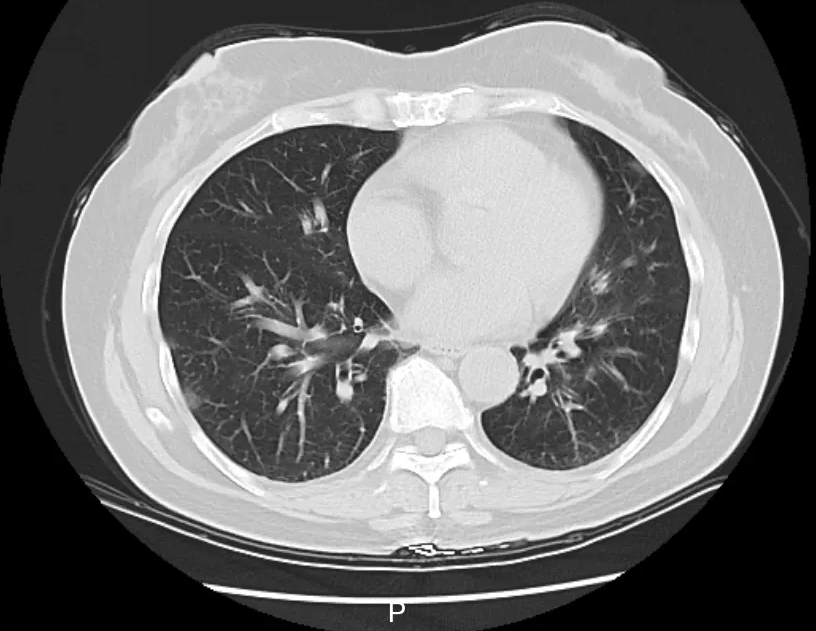

庞医生判断,李阿姨大概率是得了传染性较强的呼吸道疾病,立即给她安排了血常规、相关病毒抗原检测,以及更清晰的肺部CT检查,以便进一步了解病情。